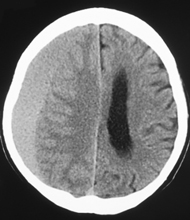

脳挫傷

血腫が脳実質内にできるもので、脳実質や脳実質内血管の損傷によって生じます。主に、前頭葉や側頭葉にみられますが、軽症例では頭痛や軽度の意識障害を認めます。

中等症以上では、運動麻痺や失語症(言葉が理解できなかったり、話せない症状)などの症状や重度の意識障害がみられ、重症例になると、手術による除去が必要になります。

一般的に生命予後はよいのですが、運動麻痺や言語障害などの後遺症を残すことが少なくありません。